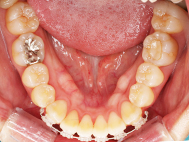

After

治療詳細

左上前歯が下の歯の内側に入っているのが気になるとの事で来院されました。目立たない矯正治療を希望しているとのこでした。 上顎の装置は、歯の裏側(リンガル装置)で下顎は表側で矯正治療を行いました。口を閉じた時、上の前歯が内側に入っている為に下の歯を前に押し出している状態でした。その為、上の歯を前に出すだけではその歯が下とのかみ合わせの関係で、前に飛び出すような治療となってしまいます。 今回の症例ではシュミレーションを見て頂き、下の歯も治療し、内側へ下げることによって上の歯も飛びだすことなく、キレイにおさまることを説明し、上下一緒に矯正することをお勧めさせて頂きました。